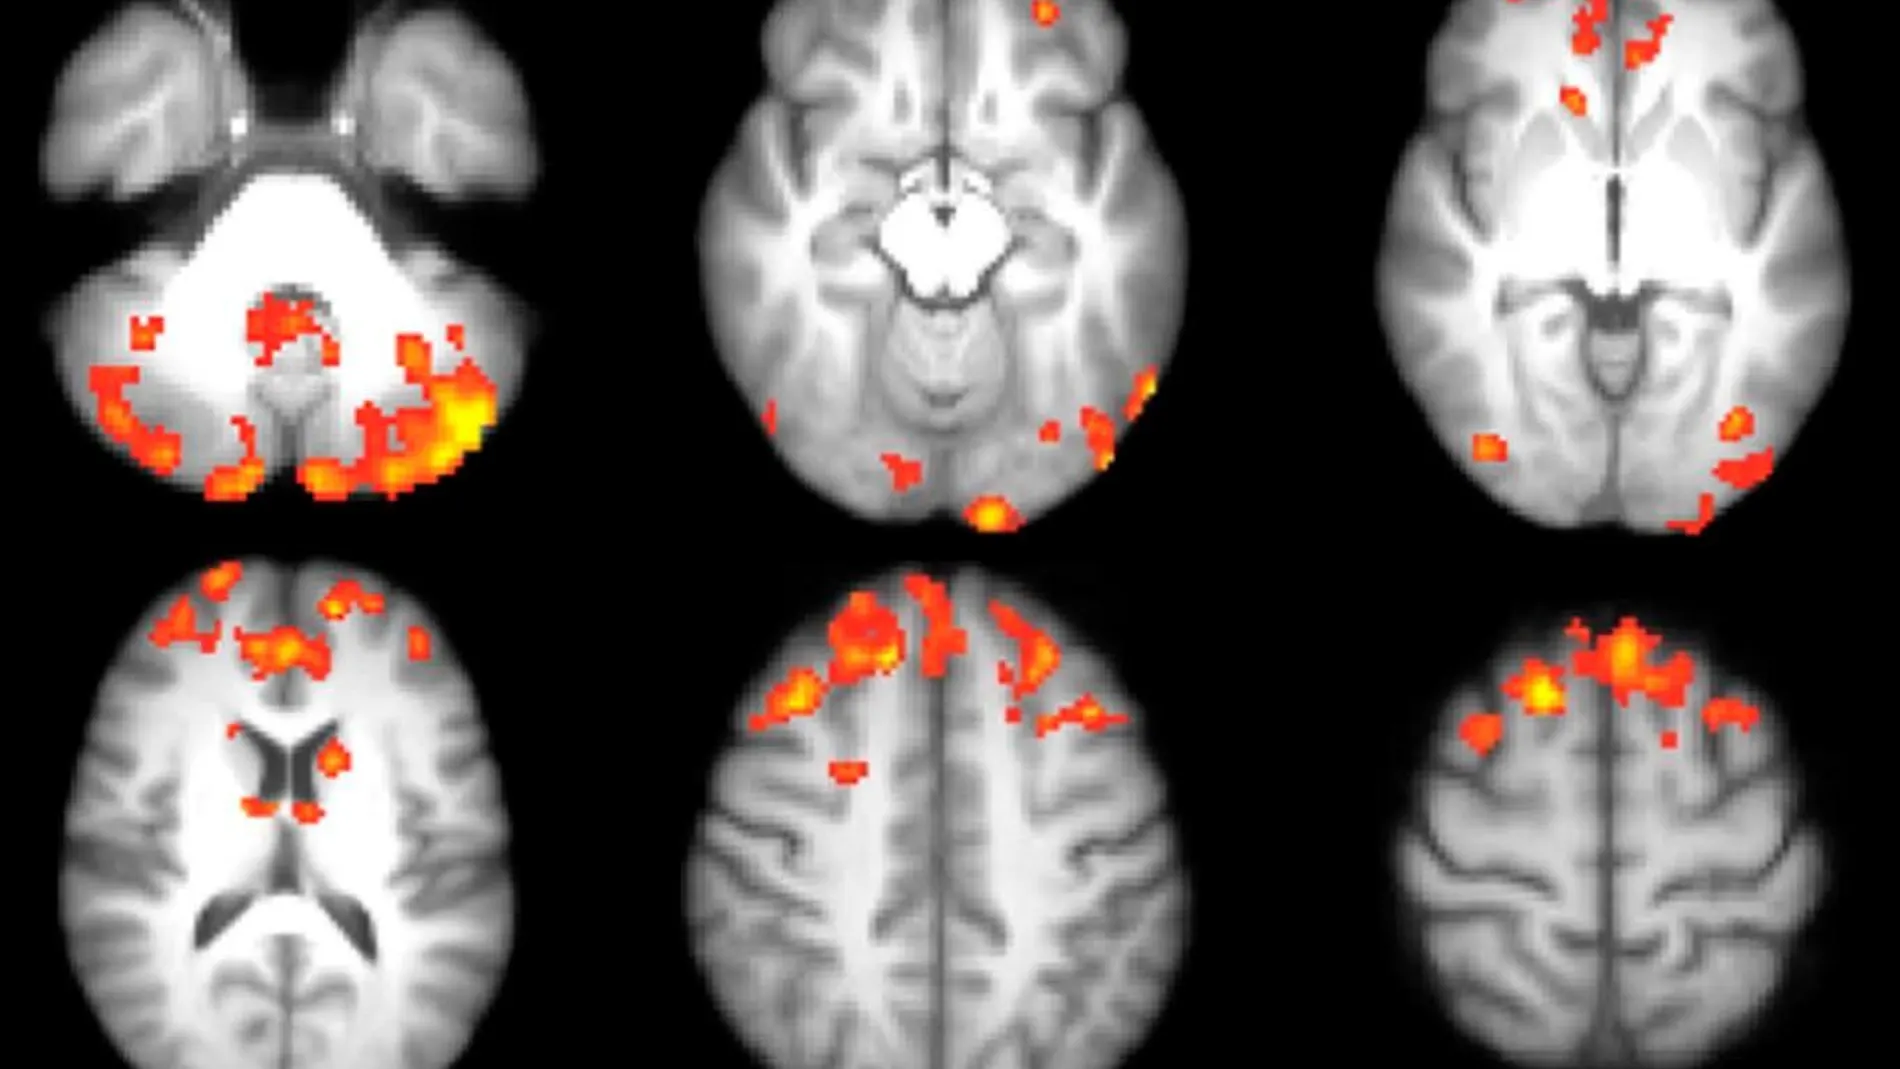

Un nuevo hallazgo de investigadores franceses del Instituto Pasteur publicado en «EMBO» arroja luz sobre la posible causa de la aparición de la esclerosis múltiple (EM). Han demostrado que virus antiguos están involucrados en la respuesta de defensa inflamatoria aguda, que puede contribuir a la aparición de esta enfermedad. El sistema de defensa que, generalmente, nos protege de la agresión externa enciende sus propias células y los ataca por razones que aún no se conocen. La EM es autoinmune, inflamatoria e incurable y provoca daños irreversibles en el cerebro y la médula espinal. También está asociada con la reactivación de virus antiguos, que se insertaron en nuestro ADN durante la evolución de la humanidad. Christian Muchardt, responsable de la Unidad de Regulación Epigenética del Instituto Pasteur ( París), destaca que su estudio “muestra que la reactivación de virus antiguos no corresponde a un fenómeno infeccioso, sino a una respuesta de defensa del cuerpo ante un fenómeno inflamatorio agudo”. Desde hace tiempo Muchardt estudia el papel de la epigenética en la aparición de diversas enfermedades como cáncer o EM. Es autor de importantes contribuciones sobre el papel de las maquinarias de remodelación de la cromatina en la transformación celular. Como es sabido, las secuencias virales se neutralizaron durante la evolución y ya no representan una vía de infección. Pero estas secuencias son una fuente de ADN externo que contiene información sobre el comportamiento del virus. Por lo tanto, las células han podido controlar estas secuencias para detectar infecciones lo más rápido posible y activar sus genes de defensa durante un ataque. Estas secuencias virales se usan para controlar los genes de defensa en las células madre. Están latentes en las células adultas y son las más tradicionales las que se activan. Al examinar muestras de pacientes con EM observaron que las secuencias reguladoras de origen viral emergieron de su estado latente y fueron responsables de la expresión anormal de varios genes proinflamatorios.